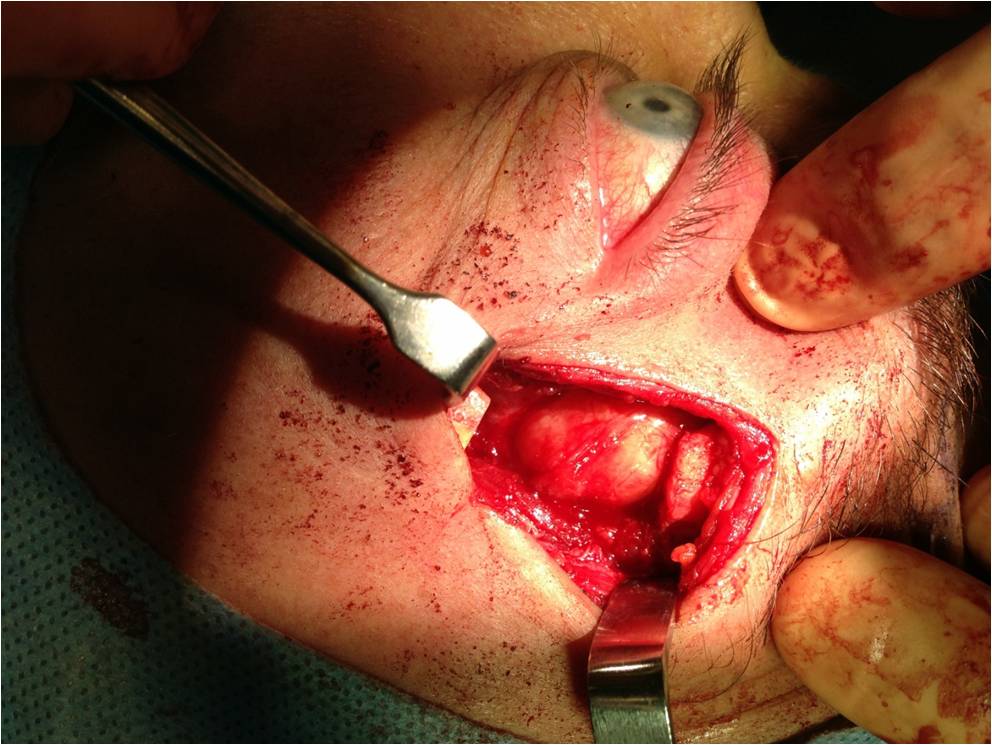

Curative treatment of PALG is complete excision with an intact pseudocapsule. In order to achieve complete excision of a lacrimal fossa tumor, a lateral orbitotomy approach is required. This surgery is performed under general anesthesia. Surgical techniques vary, but generally, the following steps are performed: a curvilinear incision (Stallard-Wright) is made over the lateral orbital wall (frontal and zygomatic bones). Temporalis fossa is exposed using periosteal elevators. The periorbital is elevated from the lateral wall and roof of the orbit with a malleable retractor. The lateral orbital rim is cut in two places using an oscillating bone saw. The lateral orbital rim is then outfractured using a large double-action Luer or Bull-nose rongeur. Using a combination of blunt and sharp dissection, the lacrimal gland is mobilized onto an island of free periorbita. Care is taken to avoid the levator and lateral rectus muscles. The gland should not be touched with forceps, always using digits or malleable retractors to mobilize it. Eventually the mass can be freed from the surrounding tissue with the pseudocapsule intact(see figure 8). [5],[12]